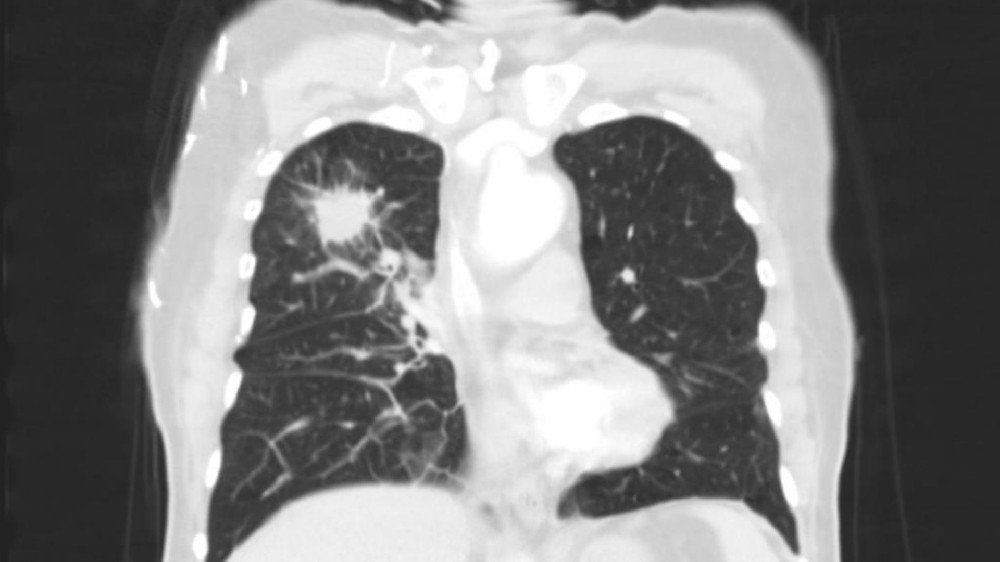

肺癌

在傳統化療和放射治療失敗後,4D 治療的機器人微波消融術 精確度 針對我的肺部轉移腫瘤,零併發症。結合新陳代謝重整 禁食 + 補充酮 和定時免疫治療 節奏我的腫瘤在三個月內縮減了 70%。我現在已是 NED(無病徵),可以繼續遠足大嶼山!"

陳先生,62 歲

結腸癌肺轉移